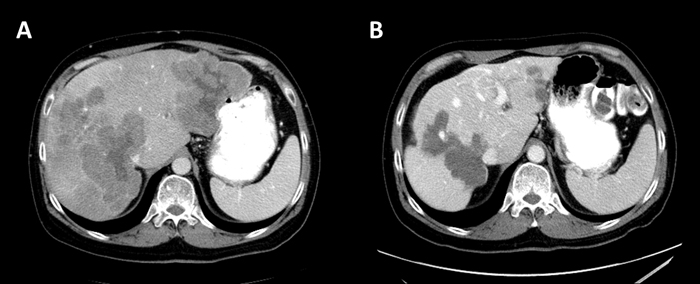

Due to the patient’s prior rectal bleeding and in-situ primary malignancy, FOLFOX was initiated with bevacizumab omitted. After 4 cycles of treatment, interval CT scan showed progression of the hepatic metastases and rectal mass according to the Response Evaluation Criteria in Solid Tumors (RECIST) version 1.1 guideline [7]. The patient’s treatment was changed to FOLFIRINOX, with an initial partial response (PR) after 4 cycles. However, after 8 cycles the patient once again demonstrated progressive disease in the liver and rectum. The patient was subsequently started on regorafenib at a dose of 120 mg per day for 3 weeks each 28-day cycle as per MD Anderson’s institutional dosing practice. Interval CT scan of abdomen after 2 months showed a dramatic response. Hepatic metastases decreased in size from 9.8 to 7.7 in the left lobe and 11.6 to 9.3 centimeters (cm) in the right lobe which was confirmed after 4 months. He continued on treatment without any dosing modifications. After 10 months of regorafenib, he required a dose reduction due to grade 2 hand-foot skin reaction (HFSR) which was most pronounced on the third week of each cycle. Subsequently, his dose was changed to 120 mg per day for the first two weeks and 80 mg per day for the third week. After 15 months of treatment, a flexible sigmoidoscopy was performed and showed an ulcerative non-obstructive mass at the site of the primary tumor which was biopsied and confirmed residual poorly differentiated adenocarcinoma. A repeat 200 gene NGS panel was performed on this biopsy and identified KRAS G12S, TP53 R273C, and APC I742fs* which were previously reported at time of diagnosis. However, new gene alterations were identified in ataxia telangiectasia and Rad3 related (ATR) gene at codon I774fs*; and gene amplifications in v-myc avian myelocytomatosis viral oncogene lung carcinoma derived homolog (MYCL), cyclin dependent kinase 4 (CDK4), and KRAS. Figure 1 showed the maximum response of the liver metastases after 17 months of regorafenib treatment.

Figure 1: Abdominal CT with contrast (A) at baseline showed multiple liver masses, largest 9.8x9.5 cm. in the left lobe and 11.6x9.8cm in the right lobe (B) At best response, the liver masses were 5.4x4 cm in the left lobe and 8.3x9.5 cm in the right lobe.